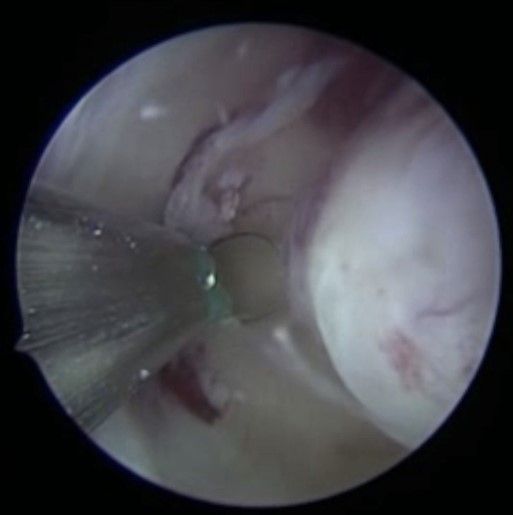

Myomentfernung per Gebärmutterspiegelung

Bei der Gebärmutterspiegelung wird die Gebärmutterhöhle mit Kochsalzlösung aufgedehnt. Eine Kamera mit integrierter Elektroschlinge wird in die Gebärmutter eingeführt. Die vorhandenen Myome können nun schrittweise unter Sicht abgetragen werden. Mittels modernsten Ultraschalluntersuchungen werden die Myome während der Operation noch einmal genau dargestellt. Bei sehr großen Befunden können zwei Operation zur kompletten Myomentfernung notwendig sein.

3 Monate nach einer solchen Operation kann mit der Kinderplanung begonnen werden. Blutungsstörungen werden in aller Regel bereits zur nächsten Menstruation gebessert sein. Der Eingriff per Gebärmutterspiegelung wird meistens in Vollnarkose und ambulant durchgeführt. Bei kleinen Myomen kann der Eingriff, dank neuester, kleinen Instrumente, auch in lokaler Betäubung ohne Narkose durchgeführt werden.